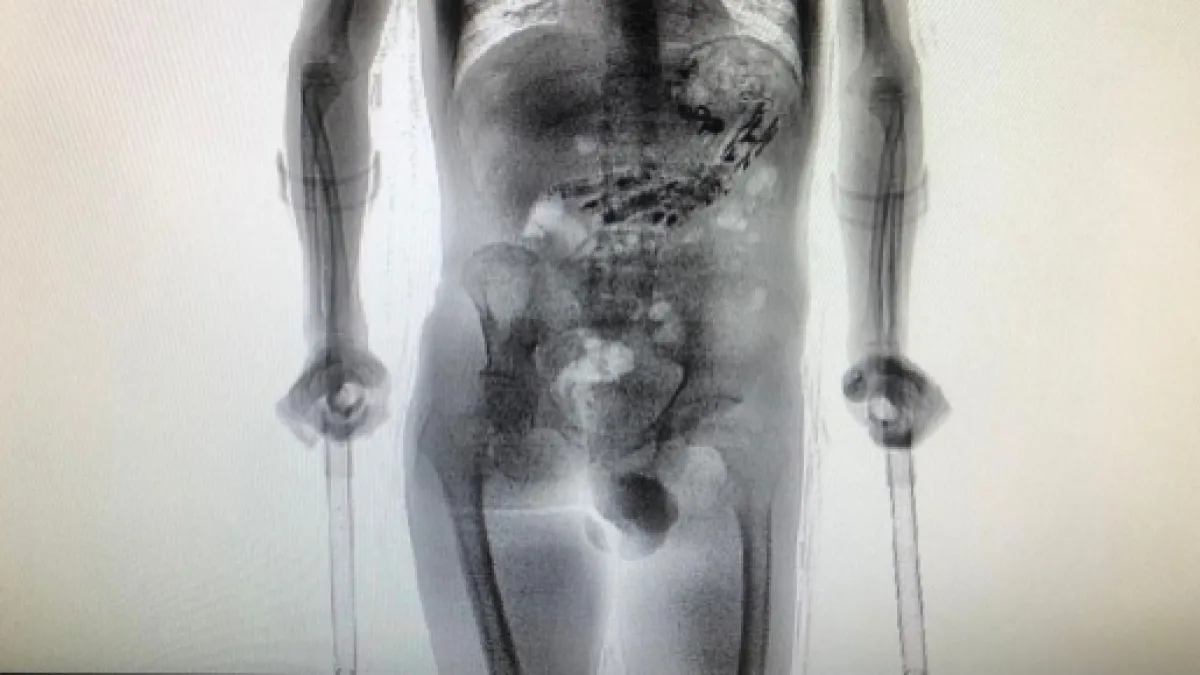

Após retornar de uma saída temporária de sete dias, o detento, que sofre de uma deficiência física, foi flagrado com 62 objetos dentro do estômago. A constatação dos objetos foi realizada por meio de um aparelho scanner.

A fim de fazerem uma vistoria mais detalhada no corpo do detento, os policiais o encaminharam para o Complexo Penitenciário do Estado, localizado na cidade de São Pedro de Alcântara, onde foi realizada uma nova inspeção de imagens com um aparelho mais moderno capaz de scanear o corpo humano e gerar imagens mais detalhadas.

Ao passar pelo scanner, foi possível detectar a presença de diversos objetos metálicos no estômago do detento.

Ao todo, foram encontrados dez aparelhos celulares e mais outros 52 objetos metálicos, tais como cabos USB, isqueiro, e uma quantidade de drogas.